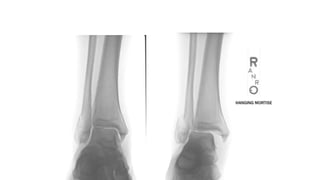

Đọc XQuang

AP

•Tibiofibular clear space : >5mm là bất

thường--> gợi ý tổn thương syndesmosis

•Tibiofibular overlap : <10mm là bất thường-

-> gợi ý tổn thương syndesmosis

•Talar tilt : > 2mm được xem như bất thường

Mortise view

•Chụp AP khi cổ chân xoay trong 10-15 độ